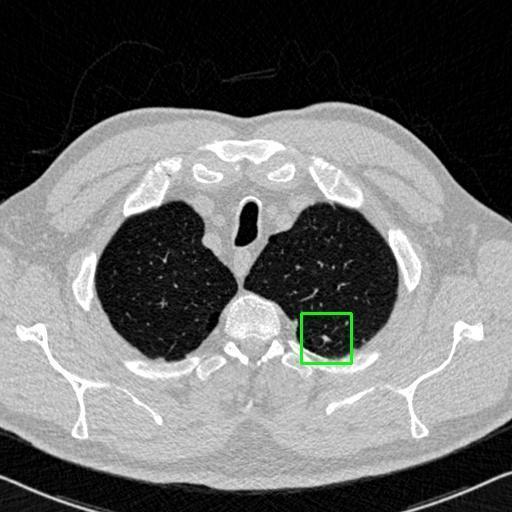

We developed an AI-based system using deep learning models for analyzing lung CT scans to detect and classify pulmonary nodules. We chose the YOLOv11 architecture for its enhanced object detection capability and adapted it specifically for medical imaging, incorporating pixel-level precision and severity classification.

Classification into three severity levels with colored bounding boxes.

Successfully built and deployed an AI model (YOLOv11) capable of detecting lung nodules in CT scans with high accuracy and real-time performance.

Designed a severity classification system that categorizes nodules into null, moderate, and severe using colored bounding boxes, assisting in rapid clinical decision-making.